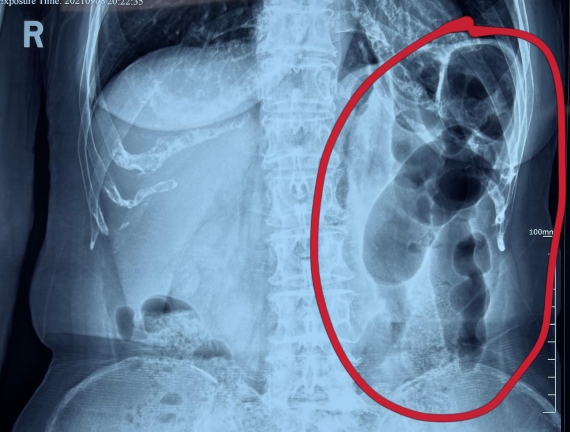

據(jù)省醫(yī)院消化病院消化二科姜子曄醫(yī)生介紹,韓大娘今年已經(jīng)73歲,家住哈爾濱市,一周前開(kāi)始腹脹腹痛,有較為明顯的左側(cè)腹部疼痛,疼痛劇烈時(shí)會(huì)出現(xiàn)左側(cè)腹部鼓包情況,排氣排便后有所好轉(zhuǎn)。韓大娘家人見(jiàn)狀將其送到了黑龍江省醫(yī)院,門診檢查腹部平片提示為左側(cè)腹部積氣,口服全消化動(dòng)力藥及通便治療后腹痛腹脹有所緩解,入院前再次突發(fā)左側(cè)腹痛加重伴有明顯腹脹,急診隨后以“腹痛腹脹原因待查”將韓大娘收入到消化病院消化二科。

姜子曄醫(yī)生熱情接待了韓大娘,為其進(jìn)行了仔細(xì)查體,除了左側(cè)腹部壓痛并未見(jiàn)明顯異常,對(duì)癥給予灌腸后,韓大娘的腹脹有所緩解,第二天姜子曄醫(yī)生為韓女士進(jìn)行了胃腸鏡檢查,也未見(jiàn)明顯異常。但此時(shí)韓大娘腹部平片結(jié)腸腸管擴(kuò)張仍然很嚴(yán)重,腹痛腹痛也沒(méi)緩解,到底什么原因呢?消化二科主任陸以霞在查房時(shí)建議繼續(xù)給予韓大娘口服全消化動(dòng)力藥,必要時(shí)灌腸治療,同時(shí)陸以霞主任在追問(wèn)病史查體時(shí)發(fā)現(xiàn)韓大娘左下腹紅色皮疹和小水泡,反復(fù)抓撓腹部皮膚部分已結(jié)痂,高度懷疑為帶狀皰疹。